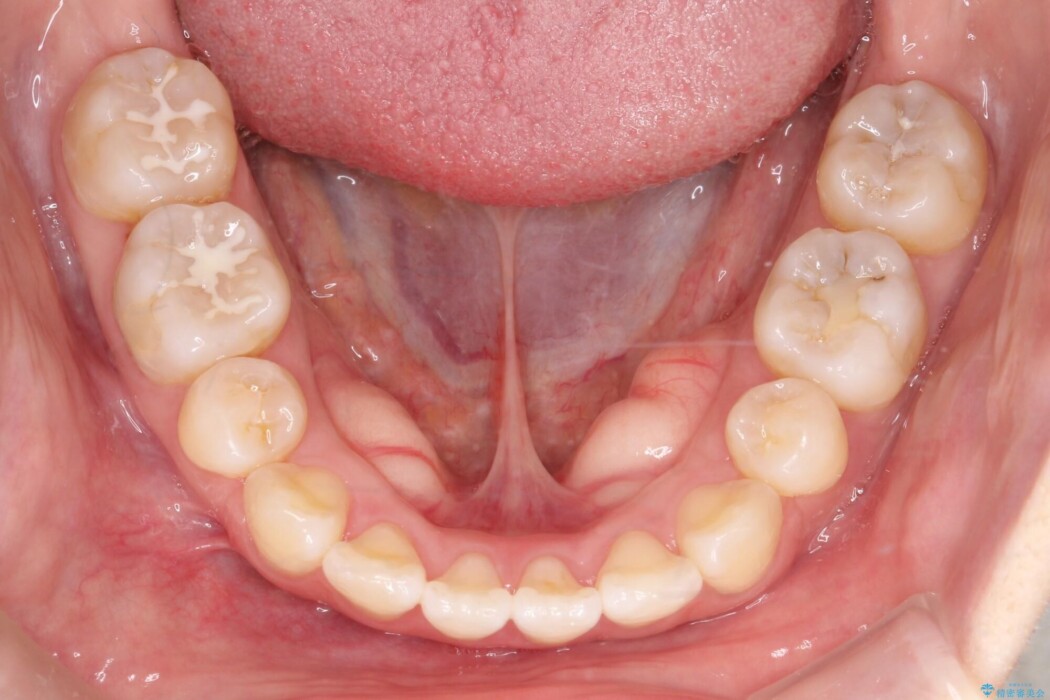

治療計画

上下顎前突のため、小臼歯の抜歯を行うことでスペースを作り、出っ張っている歯並びを下げる計画としました。